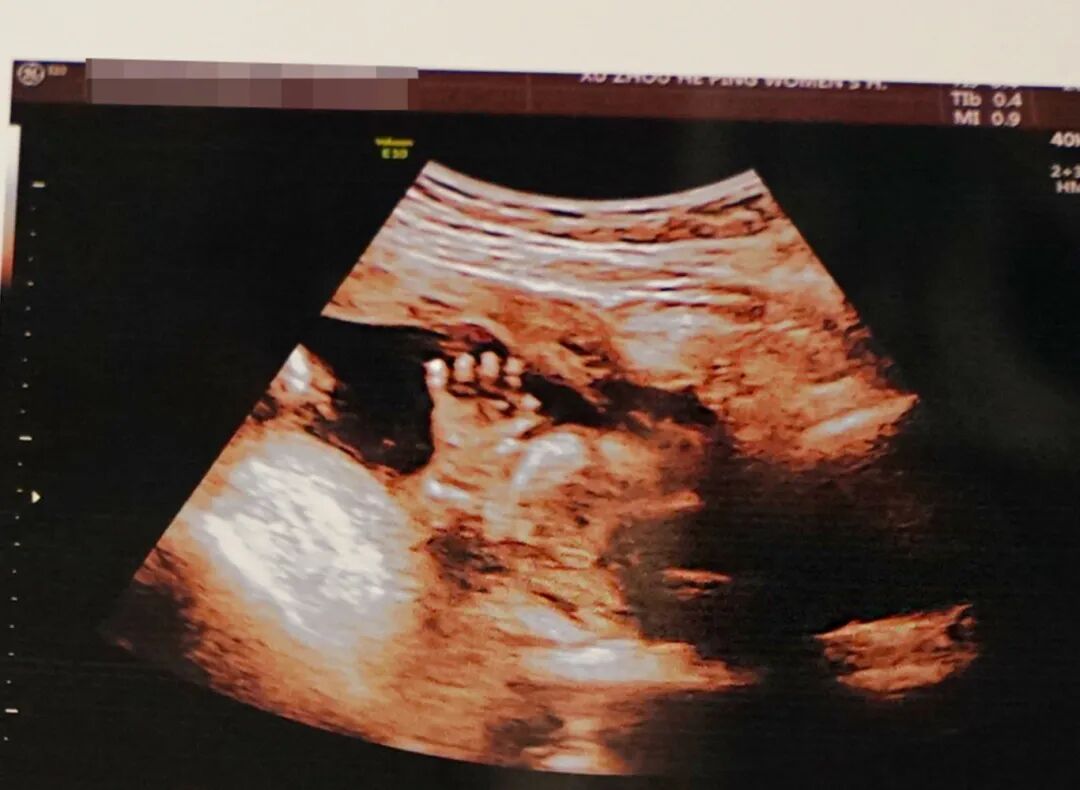

邱博士特别擅长发现那些细微、复杂的高危疑难情况,尤其是胎儿复杂畸形结构。

许多隐藏很深的、容易被忽略的细微问题,在邱博士的超声探头下都能得到清晰的解读。

疑难复杂情况胎儿影像(滑动查看更多)

邱博士曾敏锐地发现了一位孕妇潜在的脐带扭转问题。一旦脐带发生过度扭转,会对胎儿血液循环造成影响,甚至出现缺氧情况。他的及时发现为后续干预提供了宝贵窗口。